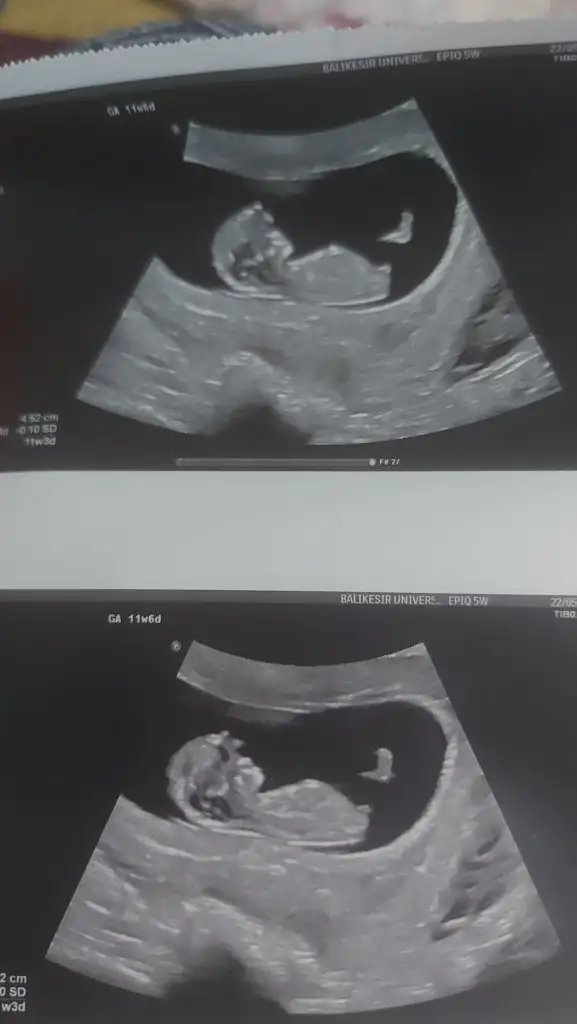

Daha önce kaybım olduğu için hiç hareketlerine bakamadım doktorumun yüzüne baktım hep olumsuz bir durum ifadesine yansıyor mu diye o yüzden bilmiyorum ama eve geldiğimde renkli ve normal ulturasyon fotoğrafi vermişti normal ulturasyon da dizlerini kırmıştı kendine doğru renkli ultrason resmindede kordonu tutmuş oynuyor gibiydieşime sordum şimdi hareketli miydi diye o da ben orada dua ediyordum gözlerim dolu dolu bakamadım dedi annem de kız çocugu kendini çok kapatır dedi gerçekten de renkli ulturasyonda kendini açmıştı kıyaslamak isterseniz renkli fotoğrafinj atabilirim

Ya bu yüzünü kapatıyor yerim ben bunuuuuu çok utangaçmaşallah Allah nazarlardan esirgesin

İnşallah gerçi nerdeyse 13 haftalık olacağız geçen gittik uyuyordu ne yaptıysa doktor uyanmadışimdi gitmeden çikolata yiyeceğim bi iki oynasın

Ay canım hadi inşallah güzel haberlerle geliriz burayaBen de cumartesi 12+ 4 olacağım inşallah cinsiyetten çok ikili test beni heyecanlandıriyir senin gittiğin hastanenin de ulturasyon cihazı bizimki ile aynı doktoruna söyle renkli fotoğraf versin çok tatlı oluyor bir de ekranı birden açtı benim doktorum birden bire gerçek bir bebek